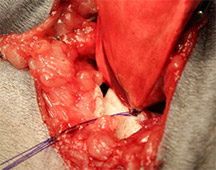

病名:肝細胞癌 手術法:内側右葉完全肝葉切除術

症例:11歳 避妊雌 MiX犬 12kg

主訴:1週間前から食欲の低下と嘔吐で来院されました。

検査:腹部超音波検査にて肝臓内側右葉に直径約12cm大の肝臓腫瘍が認められました。また、胆のうに重度の胆泥の貯留を認めました。

治療:飼い主様の希望により、肝臓腫瘍摘出手術と胆嚢切除手術行いました。肝臓腫瘍摘出は特に血管系の処理が重要で基本的な結紮技術はもちろん、超音波乳化吸引装置や血管シーリング装置などを駆使し血管を一つずつ処理して行きます。

肝臓腫瘍と胆嚢を摘出した写真です。肝臓腫瘍摘出には超音波乳化吸引装置を使用し、かなり安全に手術が可能でした。

胆嚢内にはゼリー状の内容物が詰まっていました。手術後は2日後から食欲も改善し、状態も改善しました。病理検査で肝細胞癌との診断でしたが、手術で切除しきれているとのことで、今後は無治療で経過観察中です。